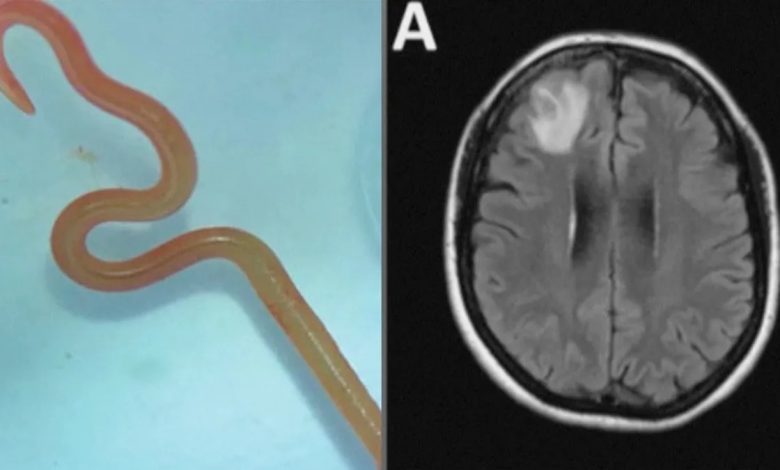

اكتشاف فريد من نوعه .. دودة طولها ثمانية سنتيمترات تعيش داخل دماغ إنسان ! ( فيديو )